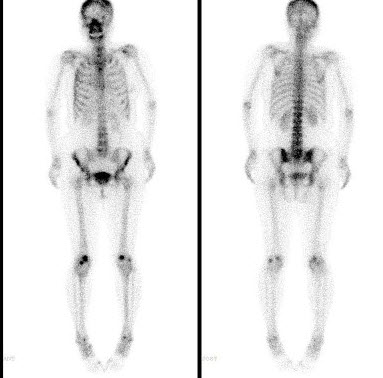

122、多项选择题

右乳癌根治术后5年,无明显不适,血清CA153正常,行全身骨显像如图,可能的诊断是()

A.多发骨转移瘤

B.骨质疏松

C.腰椎退行性改变

D.腰4、5骨转移瘤

E.大致正常的骨影像